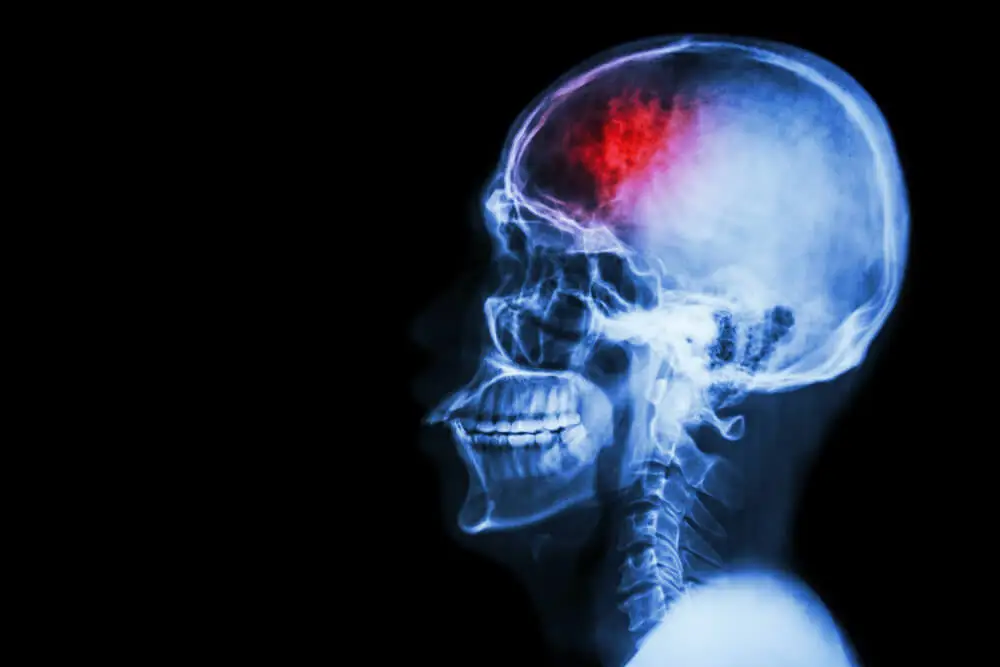

Según las últimas investigaciones realizadas sobre los daños que se producen en el cerebro por los golpes que se reciben en el cráneo, se ha podido establecer que la memoria y el pensamiento podrían verse afectados aún por los pequeños golpes que se puedan recibir en la cabeza.

En investigaciones como la realizada por investigadores estadounidenses en 2018, pudo verse un gran cambio en la materia blanca del cerebro en aquellos jugadores a los que les fue peor en las pruebas que les realizaron sobre memoria y la capacidad de aprendizaje. La materia blanca es la que se encarga de transportar los mensajes entre los diferentes lugares del cerebro.

Es decir, varios golpes por pequeños que sean pueden producir un cambio bastante fuerte en la estructura cerebral, lo que puede provocar pérdida de la memoria y dificultad para concentrarse y aprender nuevas cosas.